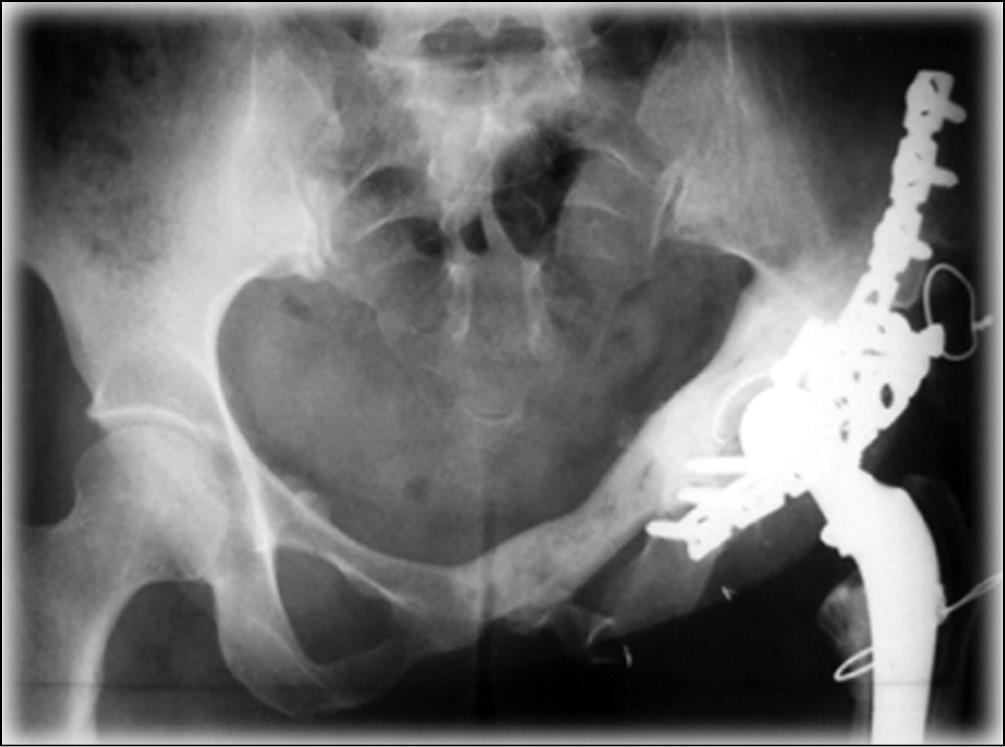

D.J. Biau и соавт. [25] в 2009 г. использовали в качестве аутотрансплантата фрагмент резецированной бедренной кости (рис. 4).

Рис. 4. Рентгенограмма костей таза после хирургического лечения. Фрагмент бедренной кости перемещен в зону резекции совместно с эндопротезом тазобедренного сустава. Фиксация осуществлена за счет металлоостеосинтеза [25]

Авторы сообщают о 13 прооперированных больных. Средний период наблюдения составил 49 мес. Послеоперационные осложнения диагностированы у 5 (38 %) пациентов. Общее количество осложнений составило 69 %. Инфекционные — 15,3 %, вывих головки эндопротеза — 23,1 %, нестабильность трансплантата — 15,3 %, перелом трансплантата — 15,3 %. C. Delloye и соавт. [24] в 2007 г. выполнили реконструкцию параацетабулярной области аллографтами у 24 пациентов. Осложнения диагностированы у 50 % прооперированных больных, при этом наиболее распространенными были инфицирование раны и несостоятельность аллотрансплантата. Функциональный результат по MSTS составил 73 %.